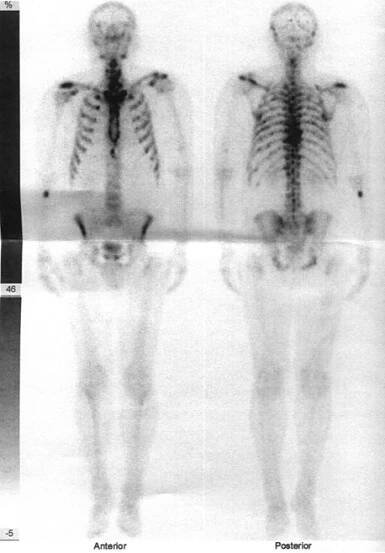

Obr. č. 2: Celotělová scintigrafie skeletu v přední a zadní projekci

Obr. č. 2: Celotělová scintigrafie skeletu v kostní fázi vyšetření – mnohočetná ložiska zvýšené kostní přestavby ve výše uvedených lokalizacích.